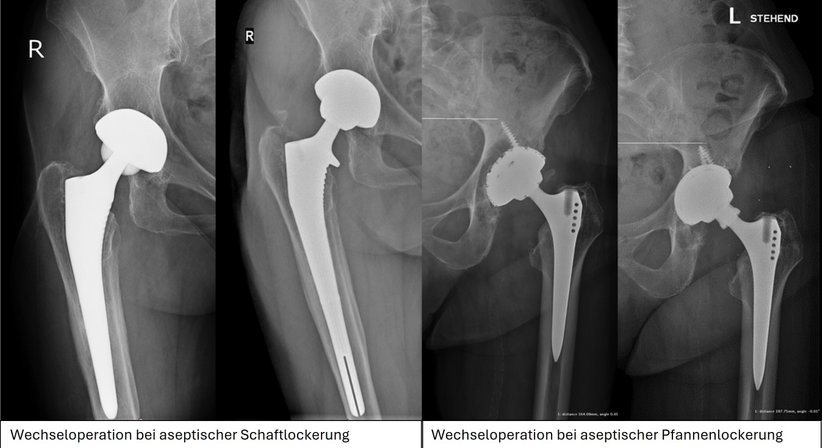

Bei einer Wechseloperation werden, je nach Indikation, entweder einzelne Teile/Komponenten der implantierten Prothese (Gleitpaarung, Pfanne, Schaft), oder auch das komplette Implantat ausgewechselt. Je nach Knochenverlust können spezielle Verankerungstechniken (Schrauben, Zement, 3D gedruckte Implantate) notwendig werden. Knochendefekte können durch künstlichen Knochen oder Fremdknochen (sogenannter Spenderknochen/Allograft) wieder hergestellt oder aufgefüllt werden.